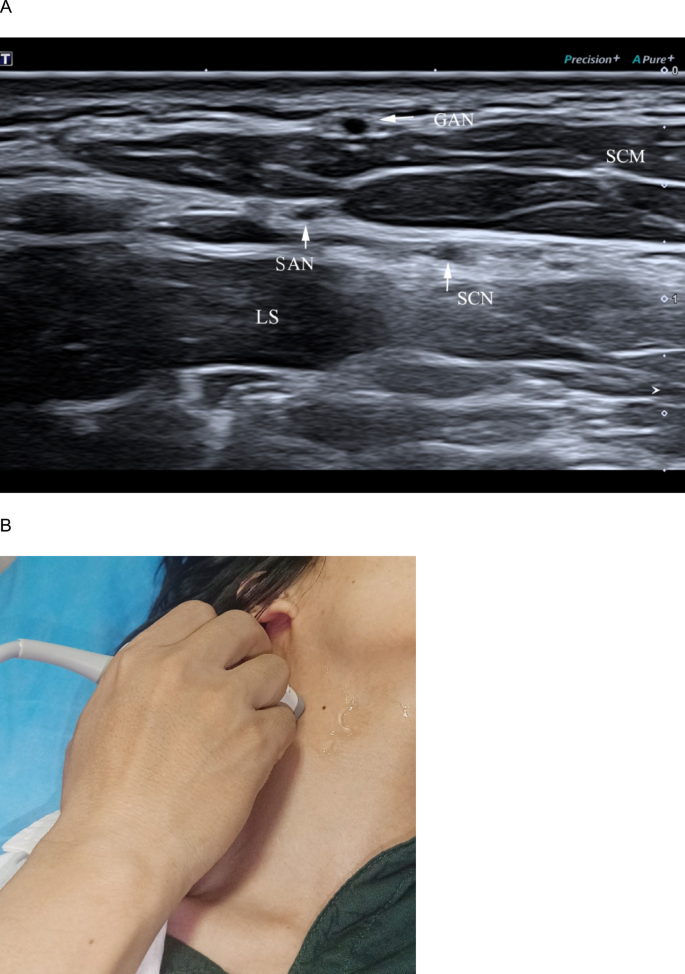

Identifying the short axis of the spinal accessory nerve (SAN) at S3. A Short-axis ultrasound at S3 shows the SAN (arrow) posterior to the sternocleidomastoid muscle (SCM) and superficial to the levator scapulae (LS); the great auricular nerve (GAN, arrow) runs along the SCM surface, and the supraclavicular nerve (SCN, arrow) courses medial to the SAN, extending posterior–inferiorly over the LS. B Transducer placement is demonstrated.